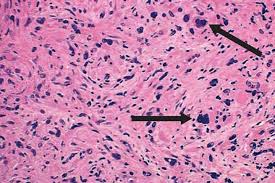

Seven cases of myelodysplastic syndrome with myelofibrosis which is defined using the following criteria. Myelodysplastic syndrome MDSMPN overlap syndromes include several uncommon myeloid malignancies that have symptom burdens and proliferative features seen in MF and are characterized by dysplastic features of MDSs. 4 absence of diffuse.

3 myelofibrosis with cellular marrow. Preconception Care First Prenatal Visit and Follow-Up Visits. Ruxolitinib phosphate may stop the growth of cancer cells by blocking some of the enzymes needed for cell growth. The Myelodysplastic Syndrome MDS is a term for a group of frequent malignant stem cell diseases mainly encountered in older individuals. Myelodysplastic Syndrome MDS is a group of disorders that gradually affect the ability of a persons bone marrow semi-liquid tissue present in many bones like backbones to produce normal blood cells. 1 Thrombocytopenia is identifiable in up to two thirds of patients with MDS with severe thrombocytopenia present in about. These abnormal cells grow quickly and cause scaring in the bone marrow and chronic inflammation. The myelodysplastic syndromes MDS are a heterogeneous group of bone marrow disorders characterized by ineffective and dysplastic hematopoiesis progressive bone marrow failure cytopenias and a high risk of transformation to acute myelogenous leukemia AML. 2 minimal or no splenomegaly.

This phase II trial studies how well ruxolitinib phosphate and azacytidine work in treating patients with myelofibrosis or myelodysplastic syndromemyeloproliferative neoplasm. The Myelodysplastic Syndrome MDS is a term for a group of frequent malignant stem cell diseases mainly encountered in older individuals. Researchers believe that myelofibrosis is caused by abnormal stem cells in the bone marrow. Myelofibrosis and Myelodysplastic Syndrome like low blood counts can be treated with blood transfusions where red blood cells or platelets are replaced. In a retrospective study of 236 patients with primary myelodysplastic syndromes MDS 130 cases 551 revealed myelofibrosis in bone marrow biopsies. This phase II trial studies how well ruxolitinib phosphate and azacytidine work in treating patients with myelofibrosis or myelodysplastic syndromemyeloproliferative neoplasm. 1 pancytopenia with less than 5 blasts in the peripheral blood.